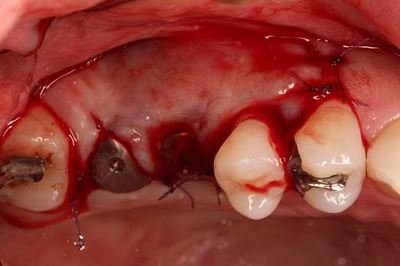

スリーブの長さがありますので狭い口腔内でドリルを挿入するのは

熟練が必要です。

まずは安全な深度までドリリングして確認します。

深度ゲージを挿入した状態でレントゲンを撮影します。

角度は想定どおりで安堵します。